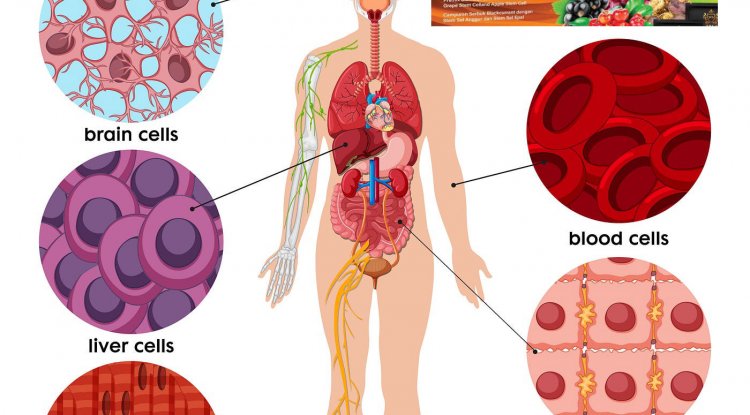

Anemia

Anemia, when red blood cell counts are low, may reveal that a tumor is bleeding into your digestive tract.

Anemia is present in 30% to 75% of colorectal cancer patients, according to 2023 research.

“There is no healthy reason a man should be anemic,” Tai said. “That is the No.1 diagnosis that we look for. And for women, if you don’t have heavy periods, you also should not have a low hemoglobin, and so you also need a colonoscopy.”